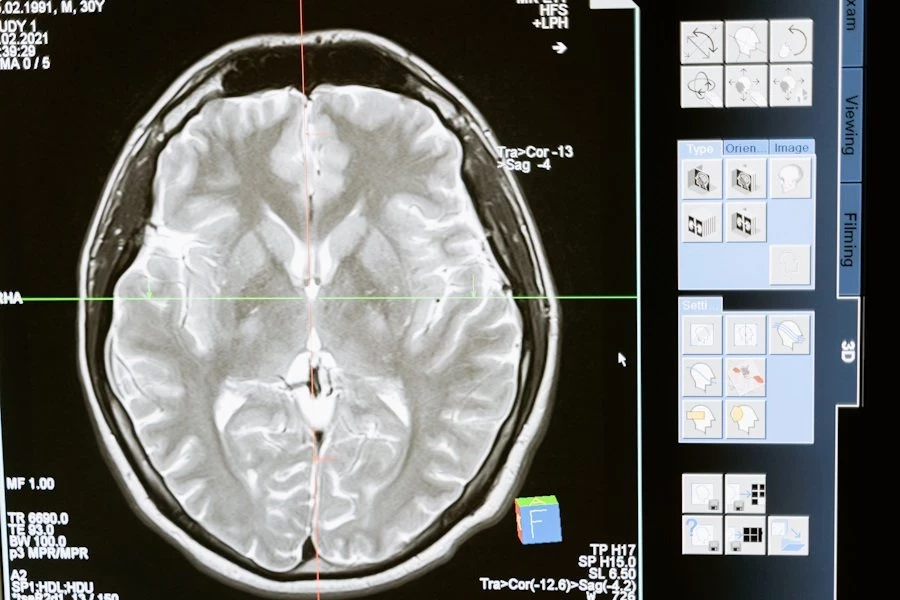

Учёные Fudan University (КНР) свершили прорыв в понимании старения мозга: исследование, опубликованное на портале Nature, выявило 13 белков, которые могут стать маркерами биологического возраста мозга. Эти белки, обнаруженные в плазме крови, связаны с процессами стресса, воспаления и регенерации, а их концентрация достигает пиков в определённые возрастные периоды: 57, 70 и 78 лет.

Для анализа использовались данные визуализации мозга 10 949 человек в возрасте от 45 до 82 лет и образцы крови почти 5 000 участников. Учёные также подтвердили причинно-следственную связь между уровнем BCAN и ускоренным старением мозга с помощью генетического метода Менделевской рандомизации.

Полученные данные открывают новые горизонты в борьбе с возрастными заболеваниями мозга, такими как деменция. Разработка методов ранней диагностики на основе анализа крови может заменить более сложные процедуры визуализации, сделав скрининг доступным и неинвазивным. Авторы исследования подчёркивают важность дальнейшего изучения поведения этих белков в различных возрастных и этнических группах, чтобы сделать выводы универсальными.